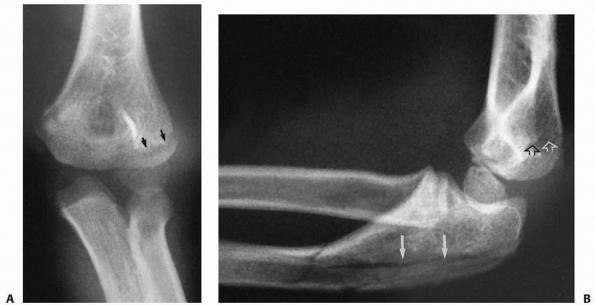

three types based on the location of the fracture line (Fig. 11-7).

Fractures associated with an elbow dislocation are subdivided into two

types. The first is based on the original concept proposed by Jeffrey42 that the fracture occurs during spontaneous reduction (Fig. 11-8A). In this case, the radial head lies proximal to the posterior aspect of the joint. The second is based on Newman’s70

concept that the fracture and displacement occur during the process of

dislocation of the elbow. In this type, the radial head lies distal to

the anterior portion of the joint (see Fig. 11-8B).

FIGURE 11-8 Dislocation fracture patterns. A.

Type D: The radial neck is fractured during the process of reduction by the capitellum pressing against the distal lip of the radial head.125 B. Type E: The radial neck is fractured during the process of dislocation by the capitellum pressing against the proximal lip of the radial head.98 C. Radiographs of a radial head that was fractured during the reduction of the dislocation (type D). The radial head (solid arrow) lies posterior to the distal humerus, and the distal portion of the neck (open arrow) is anterior. (Courtesy of Richard E. King, MD.) D. Radiograph of the dislocated elbow in which the fracture of the radial neck occurred during the process of dislocation (type E). |